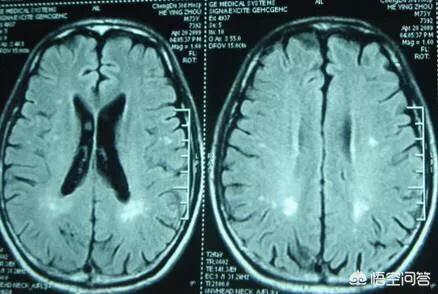

Les infarctus cérébraux caverneux sont des micro-infarctus ischémiques survenant dans la substance blanche profonde des hémisphères cérébraux et du tronc cérébral. Les foyers d'infarctus sont irrégulièrement arrondis, ovoïdes ou étroitement allongés et mesurent généralement quelques millimètres de diamètre. Dans le passé, ce phénomène n'était détecté que lors de l'anatomie pathologique du cerveau humain. Les techniques de tomodensitométrie et de résonance magnétique étant devenues plus courantes et plus avancées, la probabilité de détecter des infarctus cérébraux lacunaires a augmenté.

Il est vrai que certaines personnes atteintes d'infarctus cérébral lacunaire ne se sentent pas du tout malades et ne se souviennent pas avoir eu des symptômes d'infarctus cérébral, mais la lésion d'infarctus cérébral lacunaire n'est généralement découverte dans le cerveau qu'après une tomodensitométrie ou une imagerie par résonance magnétique (IRM) effectuée pour d'autres raisons. Dans ce cas, il existe un terme appelé "infarctus cérébral asymptomatique" dans notre département de neurologie. Cela signifie que les infarctus détectés à l'imagerie mais non cliniquement symptomatiques sont généralement de petite taille ou ne se situent pas dans des zones qui affectent la fonction. Ce phénomène n'est pas rare chez les personnes âgées.